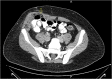

Epiploic appendagitis (EA) is an uncommon condition caused by infarction of epiploic appendages "small fat outpouchings present on the outside of the colon wall" because of torsion or thrombosis of the main draining vein. It is sometimes misdiagnosed as diverticulitis or appendicitis. Lab tests usually are normal, and the diagnosis is mainly by computerized tomography (CT) scan. Treatment is conservative as it is a self-limited condition, and the symptoms will resolve spontaneously within 2 weeks. However, surgical appendage removal could be necessary if symptoms increase or continue. Here, we report our experience with a 21-year-old male patient, who presented with a 1-day duration of localized right lower quadrant (RLQ) abdominal pain within 18*10 cm incisional hernia, imaging revealed signs of epiploic appendages infarction within the huge incisional hernia. This case describes an atypical scenario for EA, which was successfully managed with surgery. The final pathology report confirms the diagnosis.